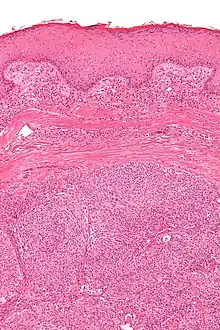

Micrograph showing an acrospiroma. H&E stain.

Hidradenoma refers to a benign adnexal tumor of the apical sweat gland.[1][2] These are 1–3 cm translucent blue cystic nodules. It usually presents as a single, small skin-colored lesion, and may be considered closely related to or a variant of poromas.[3] Hidradenomas are often sub-classified based on subtle histologic differences, for example:[4]